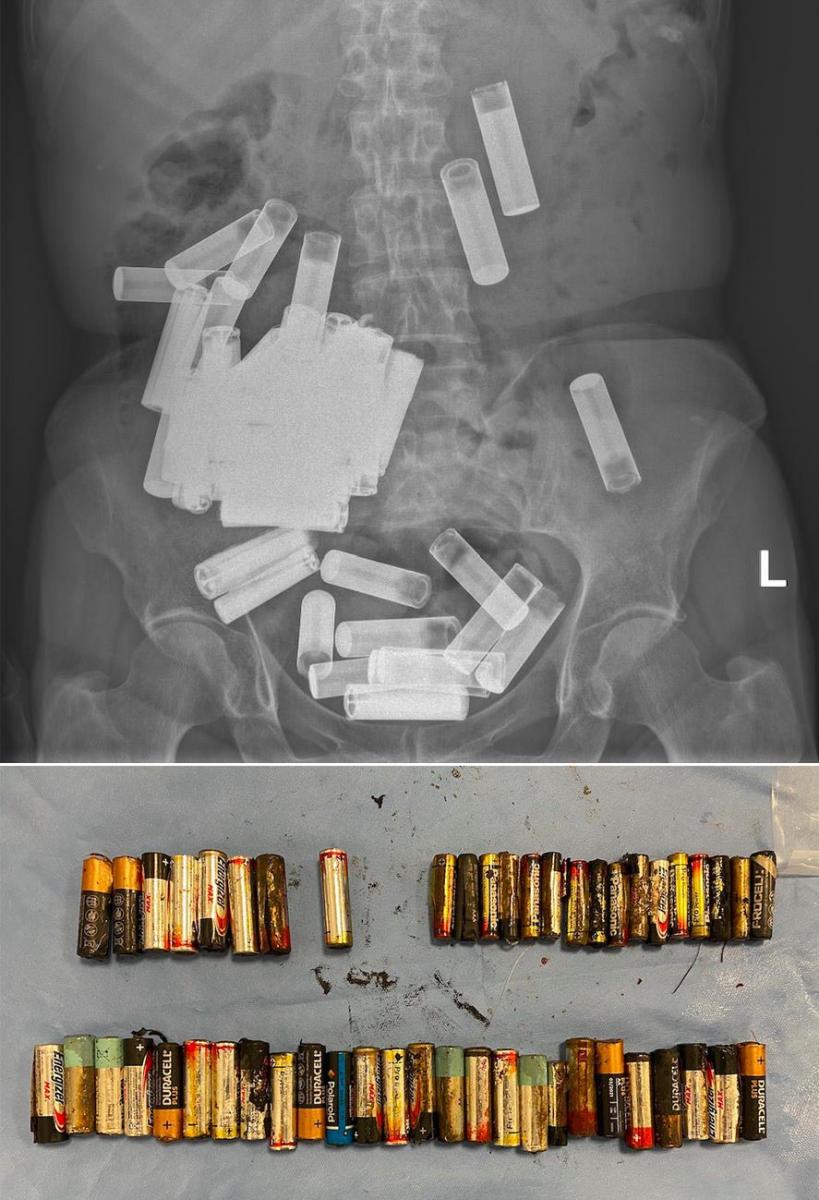

Žena z Irska spolykala rekordní počet tužkových baterií, které jí následně uvízly v břiše a přivedly ji až na chirurgii

Rentgen v dublinské Nemocnici svatého Vincenta odhalil v břišní dutině 66leté ženy množství cizích objektů, načež se od ní lékaři dozvěděli, že jde o tužkové baterie. Ani jedna jí přitom neblokovala trávicí ústrojí, proto se odborníci rozhodli počkat, zda nevyjdou přirozenou cestou.

Během prvního týdne hospitalizace se však uvolnilo „pouhých“ pět článků a žena začala trpět bolestmi. Ukázalo se totiž, že žaludek, tažený dolů tíhou baterií, se roztáhl až do oblasti stydké kosti. Při následné operaci jí chirurgové vyjmuli z břicha rekordních 46 baterií. Čtyři další baterie, uvízlé v tlustém střevě, lékaři protlačili trávicím traktem, čímž se celkový počet vyjmutých baterií vyhupl na 55 kusů. Podle psychologů je polykání baterií sice neobvyklou, ale přesto známou formu sebepoškozování. Mnohem častější jsou ale případy, kdy barerii pozře malé dítě.